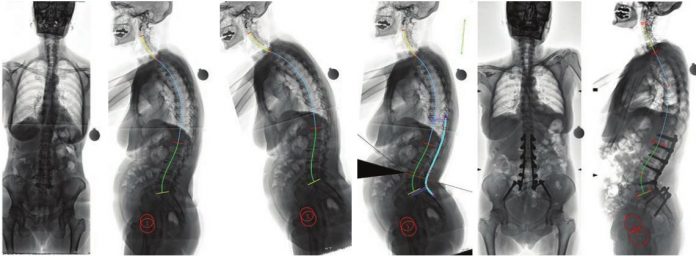

Η αντιμετώπιση των παραμορφώσεων της σπονδυλικής στήλης των ενηλίκων, ένα πολύ ιδιαίτερο και δύσκολο χειρουργικό πρόβλημα, βασίζεται πλέον στον ακριβή γεωμετρικό τρισδιάστατο προεγχειρητικό σχεδιασμό, με τη βοήθεια υπολογιστικών προγραμμάτων χειρουργικού σχεδιασμού. Με την τεχνική αυτή, σχεδιάζεται με απόλυτη ακρίβεια η χειρουργική επέμβαση, ενώ προκατασκευάζονται και υπάρχουν διαθέσιμα στο χειρουργείο εξατομικευμένα, για τον κάθε διαφορετικό ασθενή, υλικά σπονδυλοδεσίας.

Επιπλέον, με την χρήση της διεγχειρητικής τρισδιάστατης νευροπλοήγησης (ρομποτική χειρουργική της σπονδυλική στήλης), είναι εφικτή η ταχύτατη, με ακρίβεια και ασφάλεια, εμφύτευση των υλικών οστεοσύνθεσης και η πραγματοποίηση ακόμη και των πιο λεπτών χειρουργικών επεμβάσεων, σε όλες τις περιοχές της σπονδυλικής στήλης, από τον αυχένα έως και το ιερό οστό. Η διόρθωση της παραμόρφωσης ελέγχεται διεγχειρητικά και ο χειρουργός έχει τη δυνατότητα επιπλέον τροποποιήσεων την ώρα του χειρουργείου, ώστε να πετύχει το καλύτερο δυνατό αποτέλεσμα.